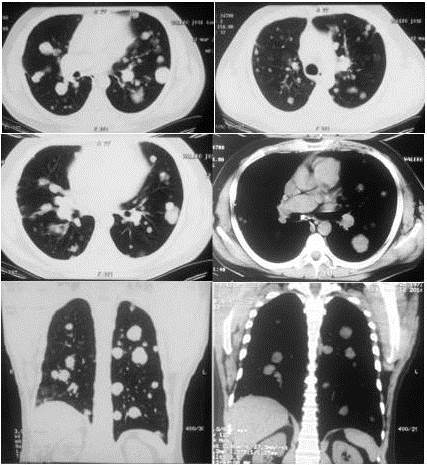

En vista de los hallazgos y la persistencia de cuadro clínico, se practica radiografía de tórax observándose en la proyección póstero-anterior (PA) múltiples nódulos pulmonares bilaterales a nivel central y sub-pleural, con broncograma aéreo, con áreas de opacidad en vidrio esmerilado (Figura1). Para completar el estudio se decide realizar una tomografía computarizada de tórax con tomógrafo BRIGHT SPEED ®de 16 detectores sin la administración de contraste intravenoso. En la ventana pulmonar se evidencia múltiples imágenes nodulares a nivel central y sub-pleural bilateral con tamaños que oscilan entre 0,6 cm y 3,1 cm, con valores de atenuación entre 23-43 UH. Se aprecia un aumento en la atenuación pulmonar con broncograma aéreo, asimismo, opacidades en vidrio esmerilado periférico bilateral, engrosamiento septos inter-lobulillares a predominio basal (Figura 2). No se observan ganglios hiliares o mediastínicos aumentados de tamaño para ser considerados patológicos desde el punto de vista tomográfico, asimismo, no se observó derrame pleural.